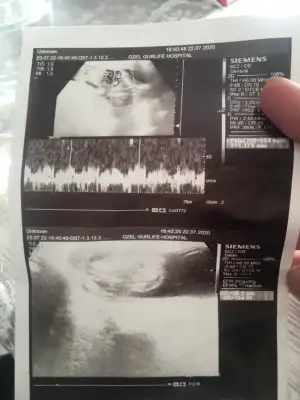

Kizlar merhaba 18haftalik gebeyim.dorduncu kez sormama ragmen doktorum cinsieti hakkinda asla kesin konuşmuyor özele gidiyorum.ister istemez uzuluyorum merak ediyorum her anne gibi haliyle...ultrason cihazida cok eski bebegi cektim diye bobregimi cekip veriyor sanki.Allahtan esim videoya almista ordan bi ss aldim.size atsam tecrubeli anneler tahmin edebilir misiniz?